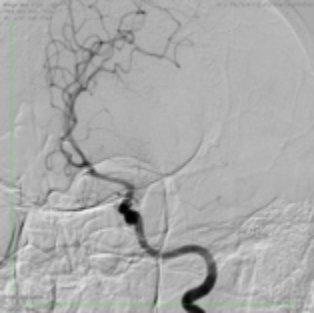

Выполнена селективная ангиография артерий головного мозга, на которой выявлена окклюзия левой среднемозговой артерии в М1 сегменте — в самом начале одной из основных артерий головного мозга (рис. 1).

![]() Рис.1 |